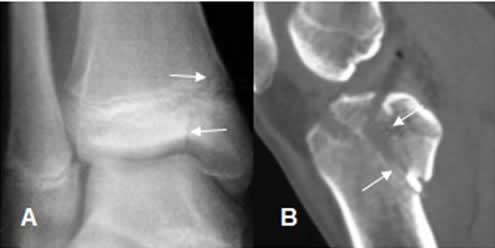

Fig 77. Salter tipo IV.

A: Rx AP y B: TAC reconstrucción sagital. Fracturas oblicuas con compromiso de las epífisis y metáfisis del tobillo y la rodilla.